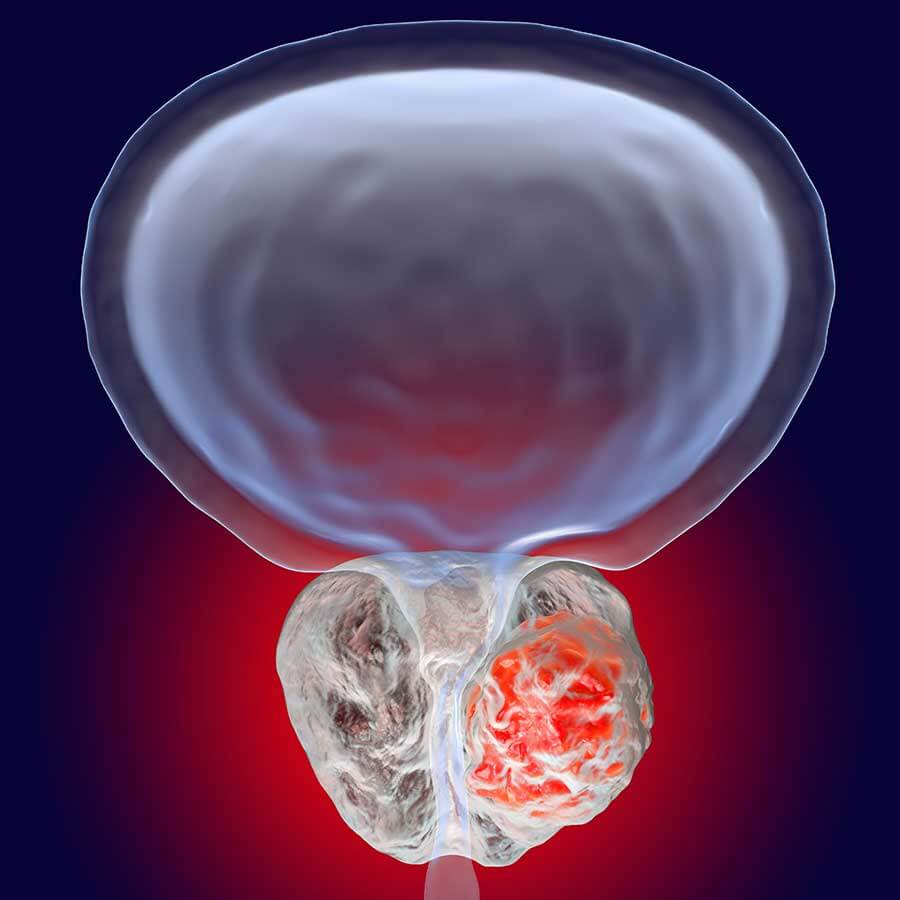

What is Localized or Locally Advanced Prostate Cancer? | PCF

Prostate Cancer | Radiology Key

A generalized overview of prostate cancer (PCa) progression …

The Spread of Prostate Cancer – Prostate Cancer Research Centre

Understanding prostate cancer